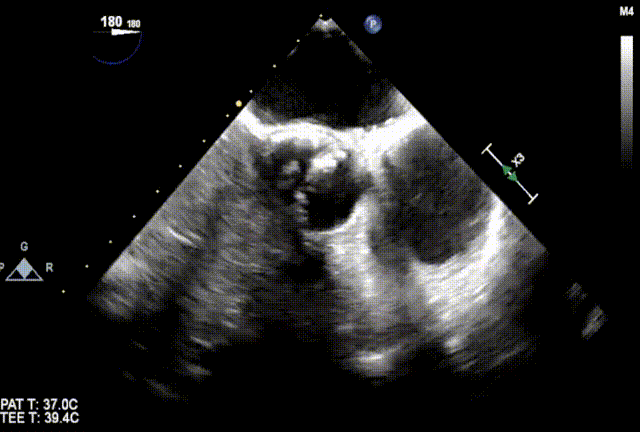

超声

• 男性,65岁;

• Type0 二叶式主动脉瓣,重度狭窄(Vmax:5.54m/s,平均压差:79mmHg,瓣口面积:0.43cm²);

• 左心房增大,左室壁增厚;

• 二尖瓣、三尖瓣反流(轻微);

• 左室壁节段性运动异常;

• 左室收缩功能正常低值(EF:54% ,EDV:83ml)。

术前食道超声